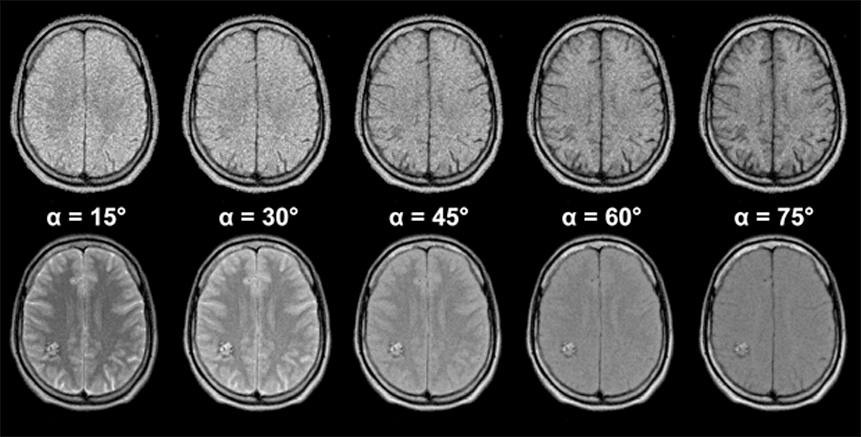

Figures 10-12 and 10-13 depict the typical signal intensity behavior of a GRE se­quen­ce, in this case a spoiled FLASH sequence. Commonly, the signal in­­ten­­si­­ties reach a maximum between 30° and 60°.

As we have seen with the signal in­ten­si­ty and contrast behavior of SE sequences, best contrast is not necessarily ob­tai­ned at the point of highest signal intensity. This is also the case in GRE se­que­nces, as the con­trast be­ha­vior of the brain images of Figure 10-13 shows. At the greatest signal in­ten­si­ty, there is poor or no contrast.

It turns out that images acquired using the Ernst angle tend to have rather poor con­trast. Higher flip angles have to be used to improve the contrast. The effect of this is a reduction of the signal left along the z-axis after the RF pulse. Thus, the sig­nal level depends on the rate at which the si­gnal recovered during TR; it is strong­ly T1-dependent. The image series in Figures 10-12 and 10-13 give an over­view of how contrast changes with in­­crea­s­ing flip angle.

Figure 10-12:

Gradient echo sequence (spoiled GRE). TR = 400 ms; TE = 20 ms. B₀ = 1.5 T. Because of the three va­ri­ables avail­able, there are nearly unlimited possibilities for changing ima­ge contrast. Generally, at low flip angles proton density dominates contrast, at high flip angles T1 becomes more important.

Images (through the brain of a normal volunteer): (a) α = 15°; (b) α = 30°; (c) α = 45°; (d) α = 60°; (e) α = 75°

Simulation software: MR Image Expert®